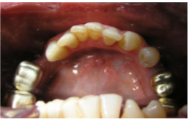

4) Restorations of upper and lower teeth